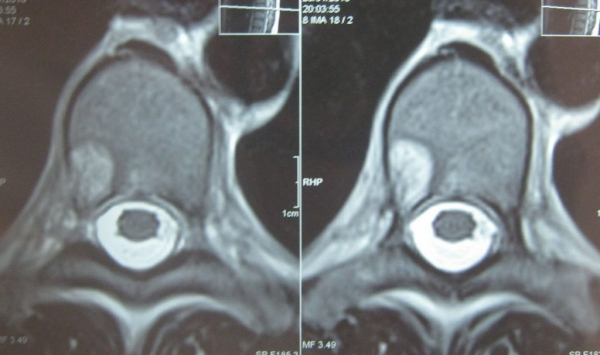

Исследование гемангиомы позвоночника чаще проходит посредством МРТ и УЗИ.

Перед тем, как начать лечение гемангиомы, важно поставить окончательный диагноз и подтвердить заболевание. Для этого больного отправляют на диагностическое исследование, которое покажет, насколько изменилось состояние позвоночника, каких размеров новообразование, какова его природа, и определит наличие или отсутствие метастаз. При гемангиоме проводят такие диагностические исследования:

- рентгенография;

- компьютерная томография;

- магнитно-резонансная томография;

- исследование сосудов позвоночника при помощи рентгенографического метода, с применением контраста.

Гемангиома тела позвонка на МРТ или КТ будет выглядеть как округлое, мягкое новообразование, которое имеет свои размеры и положение относительно позвоночника. Если опухоль переродилась в злокачественное новообразование, доктор оценит степень поражения метастазами соседних органов, а также рядом расположенных межпозвоночных отделов. Злокачественная гемангиома на КТ покажет, что трабекулярные полости не заполнены липидами, при этом присутствует мягкотканная солидная часть новообразования. Сама трабекулярная структура характеризуется неравномерностью, поражено не только тело позвонка, но и его дужки.